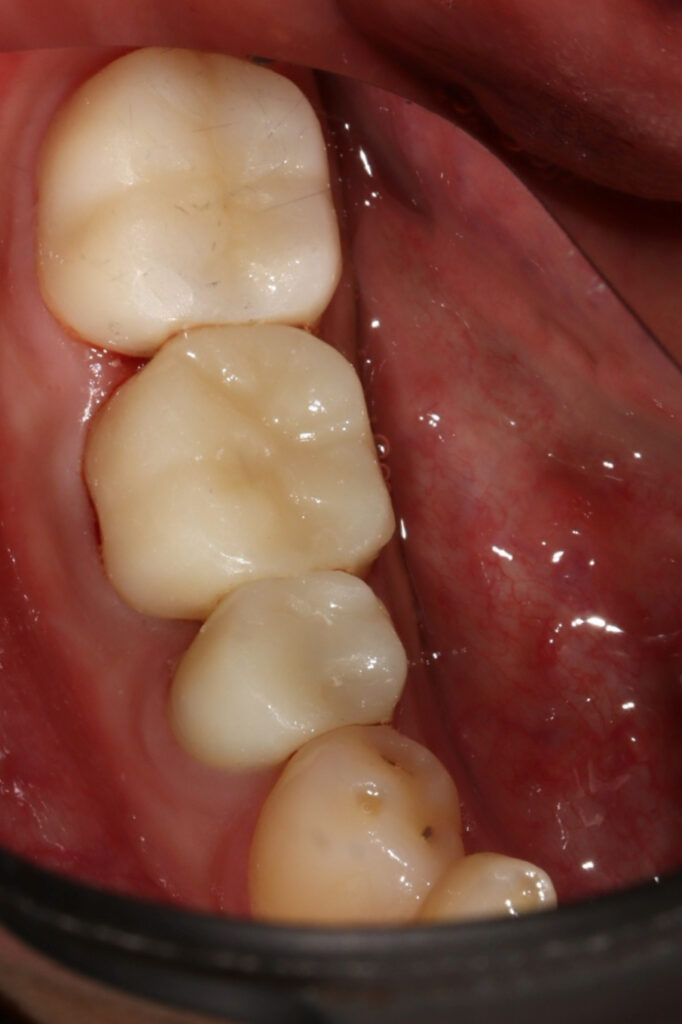

이후 크라운까지 모두

잘 마무리가 되어

저희의 바램대로

발치없이 치아를 살렸습니다.

지르코니아 크라운까지 세팅된

치료 후 모습입니다.